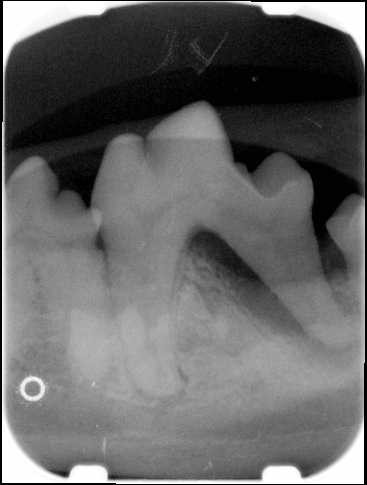

NORMAL MANDIBLE X-RAY DOG